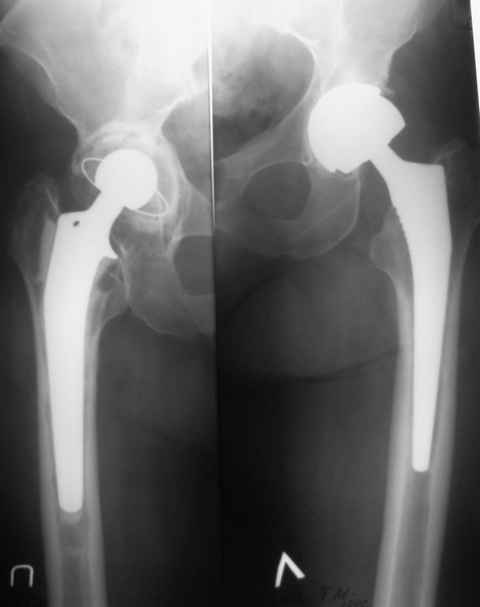

Уважаемые коллеги!Помогите определиться с тактикой лечения осложнения после эндопротезирования т\бедренного сустава ASR Пациентка 64 лет, оперирована 2,5 года назад. Выполнено эндопротезирование левого т\бедренного сустава ASR-XL. Заживление первично. 10 лет назад выполнялось цементное эндопротезирование правого т\бедренного сустава. Ч\з год после последней операции появились боли в области левого сустава, имели преходящий характер, уменьшались на фоне НПВП. В дальнейшем начались аллергические проблемы по типу стойкой крапивницы. 6 месяцев назад купированы после плазмафереза, в настоящее время не купируются. Лечение в НИИ дерматологии без эффекта. Посев пунктата (примерно 50 мл мутной серозной жидкости) без роста флоры. В анализах - Le 3,8, С-реактивный белок -24, СОЭ 25. П\операционный рубец без особенностей, температура в норме. Боли в области сустава умеренные, но сохраняются, больше беспокоят кожные проявления (зуд, сыпь). Планируем ревизию. Вопросы:1)Расценивать как металлоз или скрытую инфекцию? СРБ в 4 раза выше

Александр, тут можно предположить значительный износ чашки и как следствие металлоз. Положение впадины очень вертикальное для этого протеза, износ в зоне нагрузки идет большой, ионов навалом. Думаю можно одномоментно поменять чашку и головку, ножку оставьте. Есть возможность поставить Депьюшную керамику - еще лучше, нет - метал-полиэтилен тоже выход.

В предоперационном периоде целесообразно выполнить КТ на предмет исключения псевдоопухолевого процесса (на рентгенограммах не визуализируется). Во время ревизии желательно выполнение микроскопии, но тактика определяется не столько по наличию микробных клеток, сколько по состоянию мягких тканей в суставе - при сильно выраженных воспалительных изменениях возможно лучше перестраховаться и поставить спейсер, хотя оба компонента похоже стабильны. Если ревизия будет одномоментная, учитывая вероятную гиперчувствительность на ионы кобальта и хрома, целесообразно использовать керамическую пару трения.